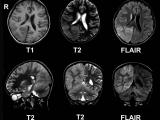

Согласно новому исследованию, тип МРТ-сканирования (T1-взвешенное), используемого для контроля сердечно-сосудистых заболеваний, может помочь в оценке агрессивности рака у детей и выявить ранние признаки ответа на лечение...

30.06.2020